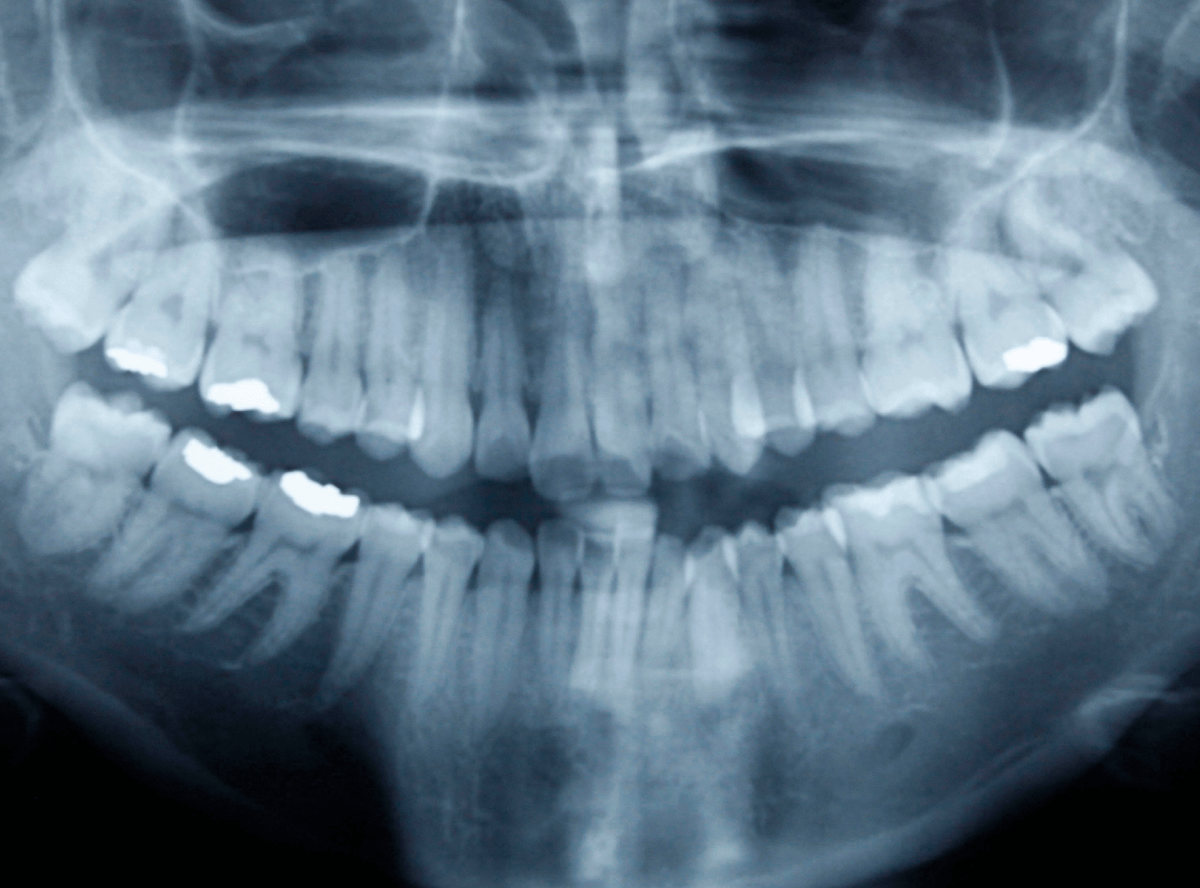

年に数回メンテナンスに来院して、お口のお手入れをし、怪しい部分はレントゲン写真で確認して、虫歯を初期段階で喰いとめる・・・を欠かさずにしていれば、神経の治療になるような事はほぼありません。

虫歯であれば、主にレントゲン撮影ですね。